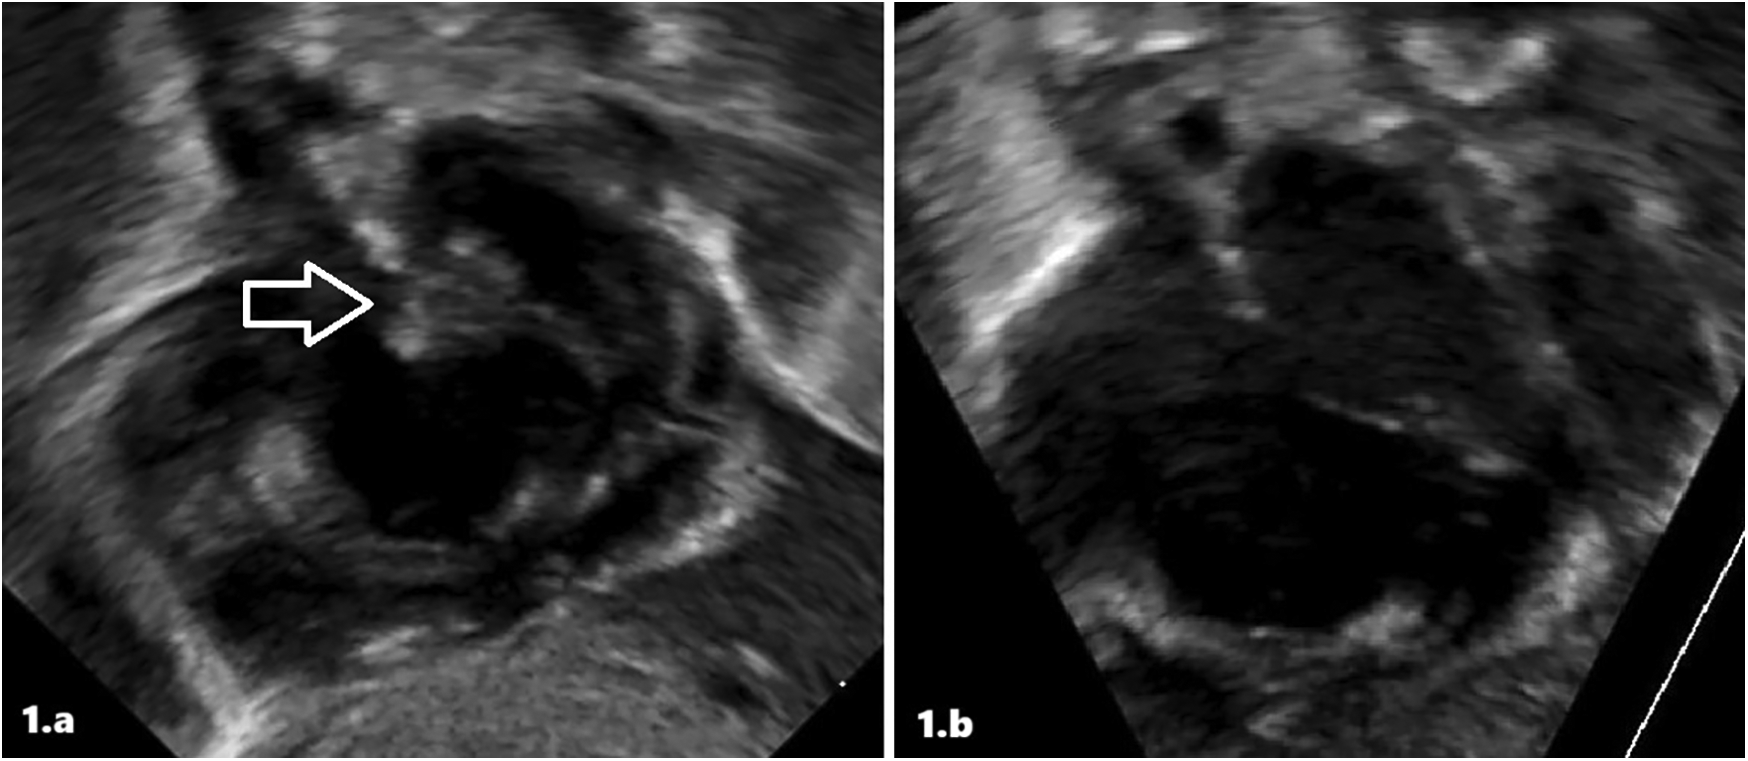

Therefore, she was immediately referred to our III-level Neonatal Intensive Care Unit (NICU). At admission, cardiovascular examination showed normal heart sound, no audible murmur, and no differences between pre- and post-ductal saturation of peripheral oxygen (measured by pulse oximetry) and normal peripheral pulses. TTE demonstrated findings consistent with persistent pulmonary hypertension (PPHN), including a dilated/hypertrophied right ventricle, left ventricular hypertrophy, and a patent ductus arteriosus (PDA) with bidirectional shunting. The diagnosis of the intra-atrial lesion was confirmed; the image was suggestive of a thrombus (Figure 1a). Enoxaparin treatment (150 U/kg twice a day subcutaneously) was started and titrated according to antifactor Xa (anti-Xa) levels monitoring. She needed to be placed on milrinone, vasopressors (vasopressin and norepinephrine), and high-frequency oscillatory ventilation (HFOV), with gradual improvement. We ruled out sepsis and viral infections.

Figure 1

Intracardiac thrombus at diagnosis (a) and after treatment (b) in patient 1 at echocardiographic scans.

The atrial thrombus was monitored daily with serial ultrasound evaluations. After 5 days of low-molecular-weight heparin (LMWH) treatment, echocardiography showed the resolution of the thrombosis (Figure 1b). Furthermore, the infant underwent a whole-body computed tomography (CT) that revealed no signs of embolism. At resolution of the thrombosis, continuous enoxaparin infusion was initially switched up to two subcutaneous infusions/day, then once/day. The infant was subsequently weaned from ventilator support, with successful extubation performed at 10 days; head magnetic resonance imaging (MRI) revealed no pathologic anomalies. The observation of ICT led to further tests being performed, and also the infant was confirmed as a heterozygous carrier of the prothrombin G20210A mutation. Enoxaparin was discontinued after 23 days of treatment. She was discharged at 34 days of life without any treatment.